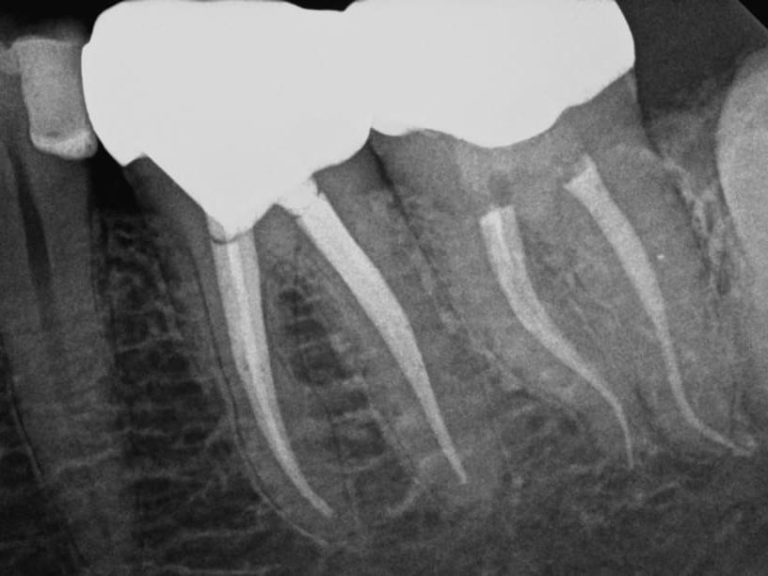

El tratamiento endodóntico, comúnmente conocido como tratamiento de conducto, es un procedimiento clave en la clínica dental para salvar dientes que están comprometidos por caries profundas o infecciones. A través de este tratamiento, se elimina la parte dañada del diente y se desinfecta el conducto radicular, permitiendo así preservar el diente natural.

Uno de los principales objetivos del tratamiento endodóntico es eliminar el dolor asociado a condiciones como la pulpitis o las infecciones dentales. Al tratar la causa del dolor, los pacientes pueden experimentar un alivio significativo y recuperar la funcionalidad de su diente, evitando así la necesidad de extracciones dentales.